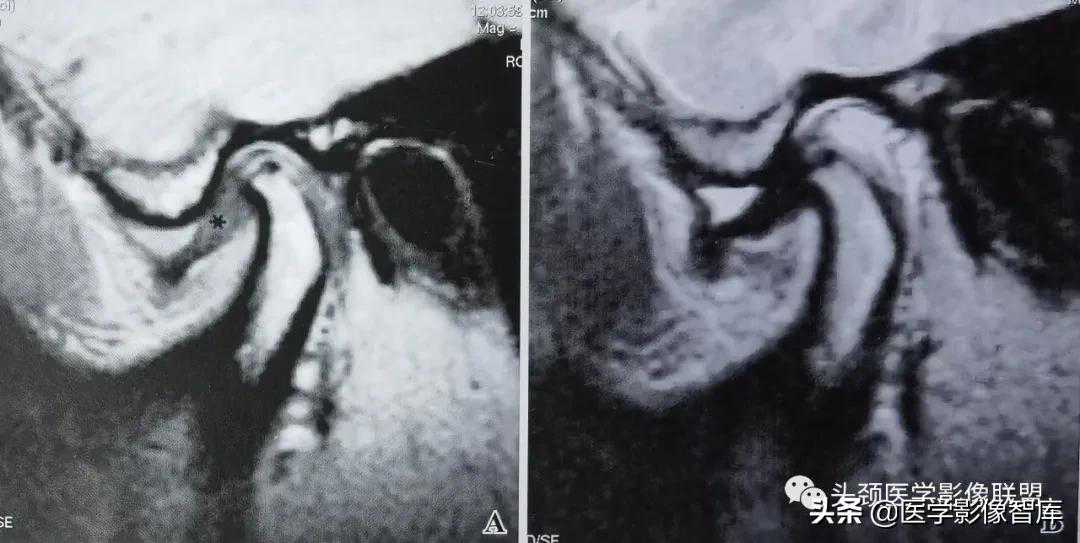

图1可复性关节盘前移

A.矢状面闭口PDWI示:关节盘后带(黑星)位于下颌髁突前方;B.矢状面开口T2WI示:盘一髁关系恢复正常。关节上腔内有少量积液。

可复性盘前移的临床主要表现为弹响。它是指闭口位时关节盘后带位置位于下颌髁突横嵴顶的前方;张口时,髁突向前移动撞击关节盘后带发生弹响,关节盘向后反跳,随后恢复到正常盘一髁关系。可复性盘前移位的MRI表现特点为:矢状面闭口位上(图1A),低信号的关节盘位于下颌髁突横嵴顶12点位的前方,关节盘双板区与后带之间的界限较为模糊;矢状面张口位上(图1B),盘一髁关系恢复正常。即下颌髁突横嵴顶12点位的上方是关节盘中间带,关节盘后带位于下颌髁突的后方。大多数情况下,可复性盘前移位时的关节盘外形少有形态上的异常改变。不完全性关节盘移位多为可复性盘移位。